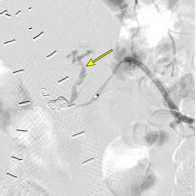

Trans-vessel Approach

Transcaval

Transarterial perigraft

Transarterial transgraft

Direct Sac Puncture Approaches

Percutaneous translumbar

Percutaneous transcaval

Percutaneous transabdominal